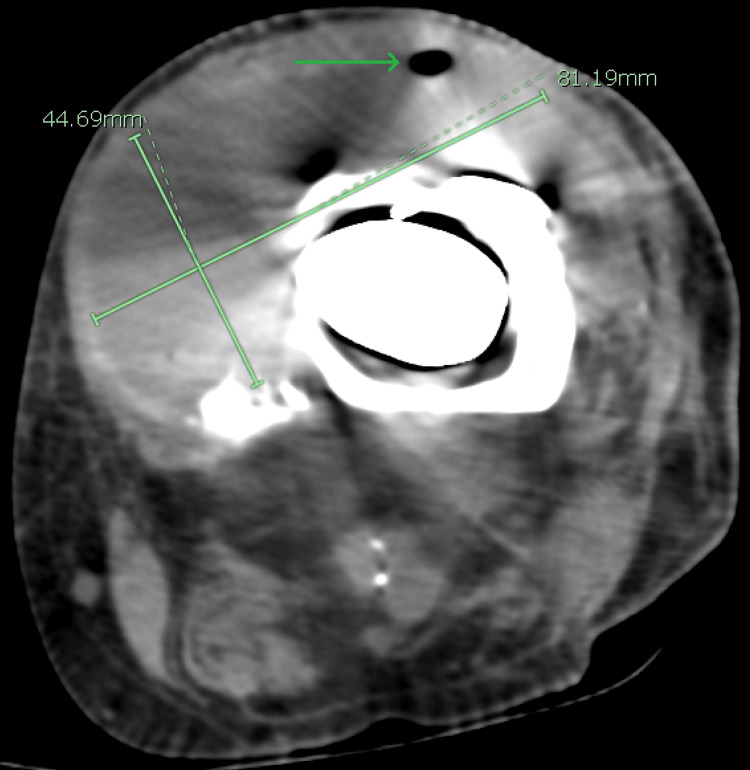

Initial laboratory investigations included a complete metabolic panel (CMP), which was unremarkable, liver function tests within normal limits, and renal function tests (RFTs), which were equally unremarkable with a blood urea nitrogen (BUN) of 21 mg/dL and serum creatinine (sCr) of 0.8 mg/dL. Glucose was 91 mg/dL, and serum calcium was at the upper end of normal, revealing a value of 10.2 mg/dL. Complete blood count (CBC) was remarkable for a significantly elevated white cell count of 28,110 cells/µL, a low hemoglobin level of 12.6 mg/dL, and a low hematocrit of 37%. A urinalysis was also completed and found to be normal as well. Imaging performed included computed tomography (CT) of the lower extremities, which showed a left knee arthroplasty with a long stem prosthesis. These images also revealed a collection of fluid with internal droplets of gas anterior to the knee measuring 8.1 cm × 4.5 cm × 12.3 cm, suggesting an abscess (Figures 1–2). The patient was empirically placed on vancomycin, piperacillin-tazobactam, and morphine.